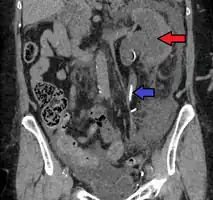

CT scan of bilateral hydronephrosis due to a bladder cancer